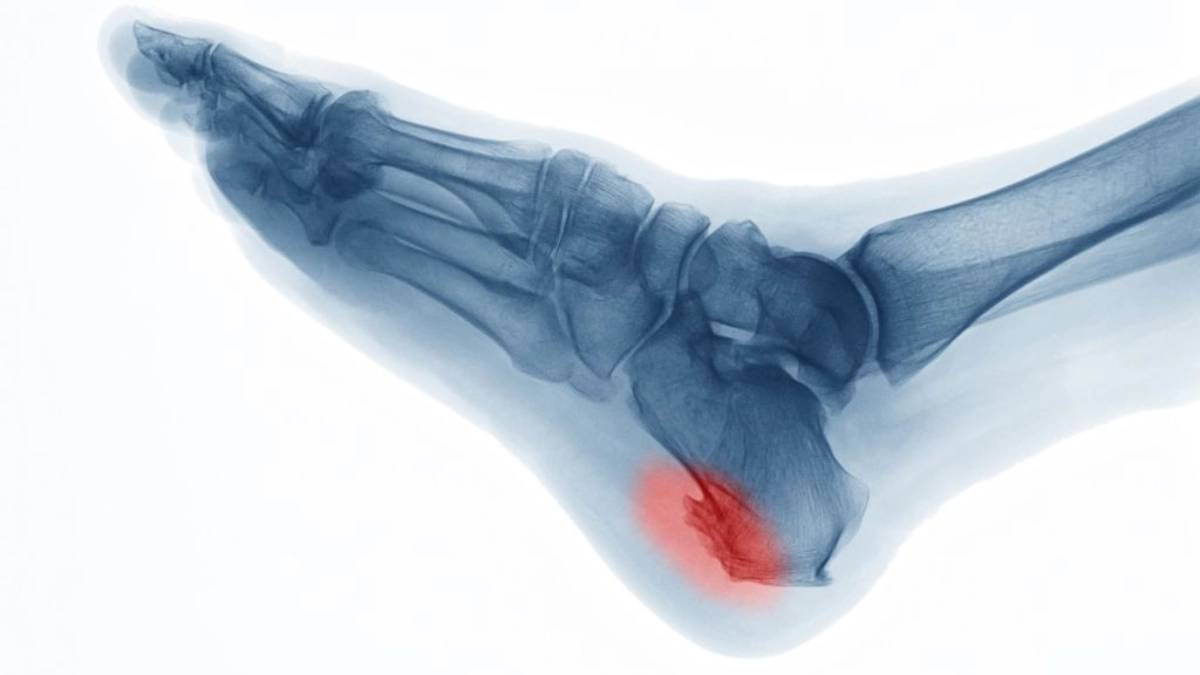

- پا، به خصوص پاشنه (خار پاشنه یا پاشنه پا)، شست پا و مچ پا.

تشخیص خار استخوان معمولاً شامل ترکیبی از بررسی سوابق پزشکی، معاینات فیزیکی، ارائه شرح حال بیمار و آزمایشهای تصویربرداری است. روش های تشخیصی تصویربرداری ممکن است شامل اشعه ایکس، سی تی اسکن یا ام آر آی باشد. همچنین، پزشک ممکن است آزمایشهای خون خاصی را برای رد سایر بیماریهایی که ممکن است باعث علائم مشابه شوند، تجویز کند.